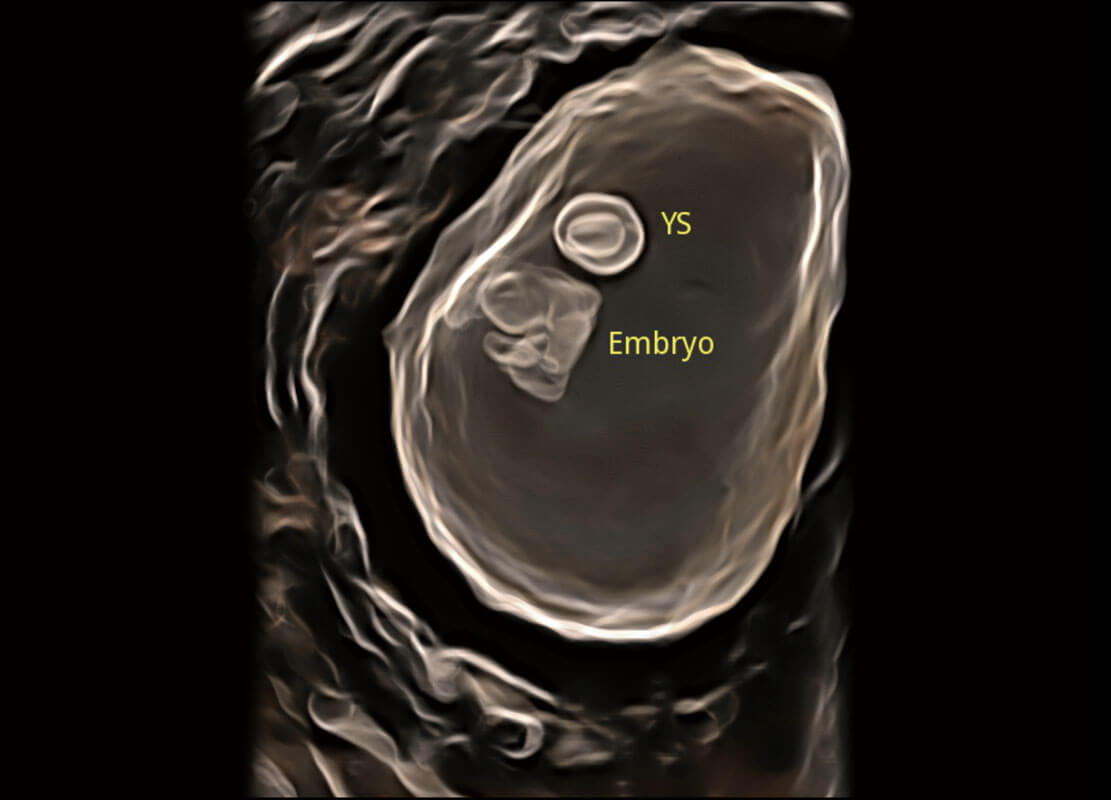

早孕筛查

根据国际妇产科超声协会ISUOG统计,早孕超声筛查结合胎儿游离染色体筛查(NIPT),能够检出大部分胎儿染色体异常疾病,P60在胎儿早孕期超声筛查中为您带来优异的图像质量。

• 早孕-胎心

• 高分辨率容积成像-早孕胎儿

• 胎儿体循环

• 光影成像-孕囊